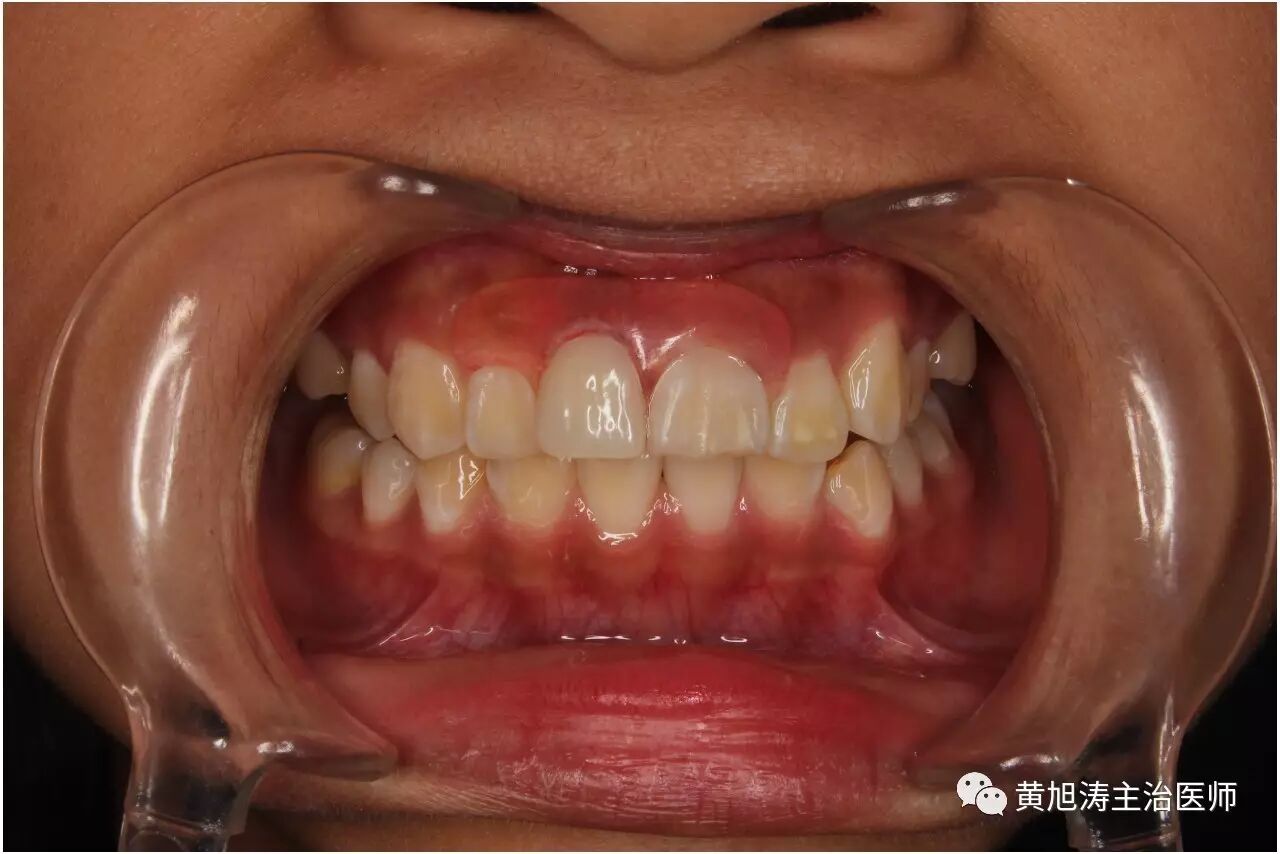

其实,不及时镶牙,危害性是很大的。

下面的视频我也听不懂他在说什么,但是视频出现的状况的确是千真万确的